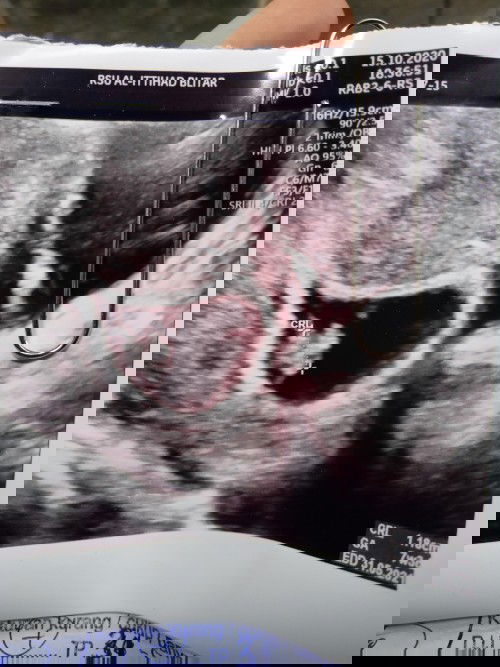

Bunda adakah yg tau...dari hptp usia kandungan saya 10w tp diusg 7w..dan janinnya dipinggir gitu

Kandungan saya yang bulat dibawah...kata dokter biasanya diatas yang bulat.dan di usg usia janin 7w pdahal kalau dari hptp 10w...adakah bunda yang pernah ngalami kesamaan